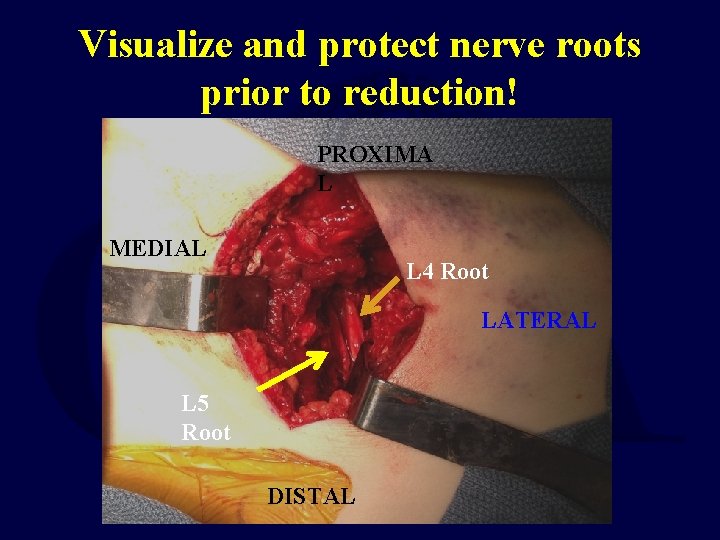

Visualize and protect nerve roots prior to reduction! PROXIMA L MEDIAL L 4 Root LATERAL L 5 Root DISTAL